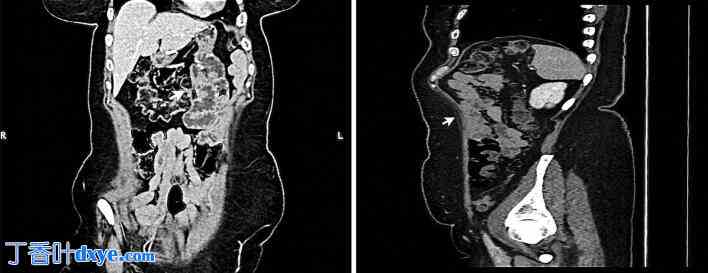

体格检查:患者生命体征稳定。腹部检查发现上腹部压痛,无腹胀。实验室检查结果无异常。腹部普通X光片正常。腹部和盆腔双对比CT扫描(图1)正常,无漩涡征,提示可能存在IH。因此,由于临床高度怀疑IH,患者入院观察。入院期间,患者未进行口服药物治疗,观察6小时后症状无改善;但患者生命体征仍然稳定。在征得患者同意后,进行了诊断性腹腔镜检查。

图 1

计算机断层扫描 (CT) 图像显示,小肠未见异常扩张、肠壁增厚或肠梗阻征象(箭头所示)。